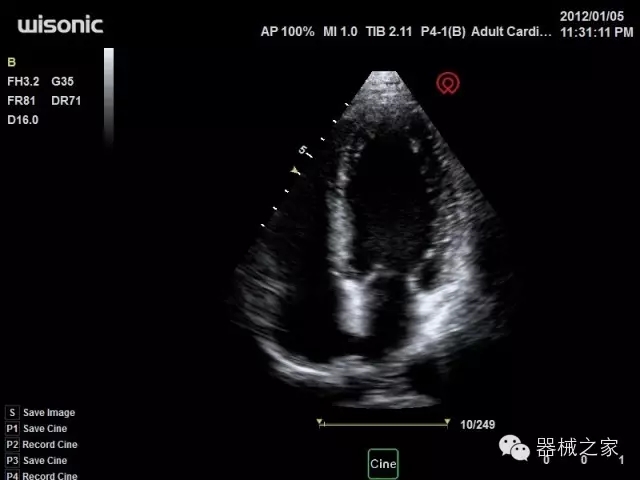

品牌:開立(SONOSCAPE)

公司簡介:

官方網(wǎng)站:www.sonoscape.com.cn

經(jīng)典產(chǎn)品:S8EXP

臨床圖片賞析

產(chǎn)品特點

優(yōu)異的成像技術(shù)

·心功能綜合指數(shù)(TEI指數(shù)):用于左、右心室整體心臟收縮舒張功能評估的測量方法;

·全方位可調(diào)M型:有利于更好的觀察心腔大小及室壁階段性運動的異常情況;

·組織多普勒成像(TDI):TDI可定量評價心肌運動,判斷是否有局部病變,還可評價早期的舒張功能;